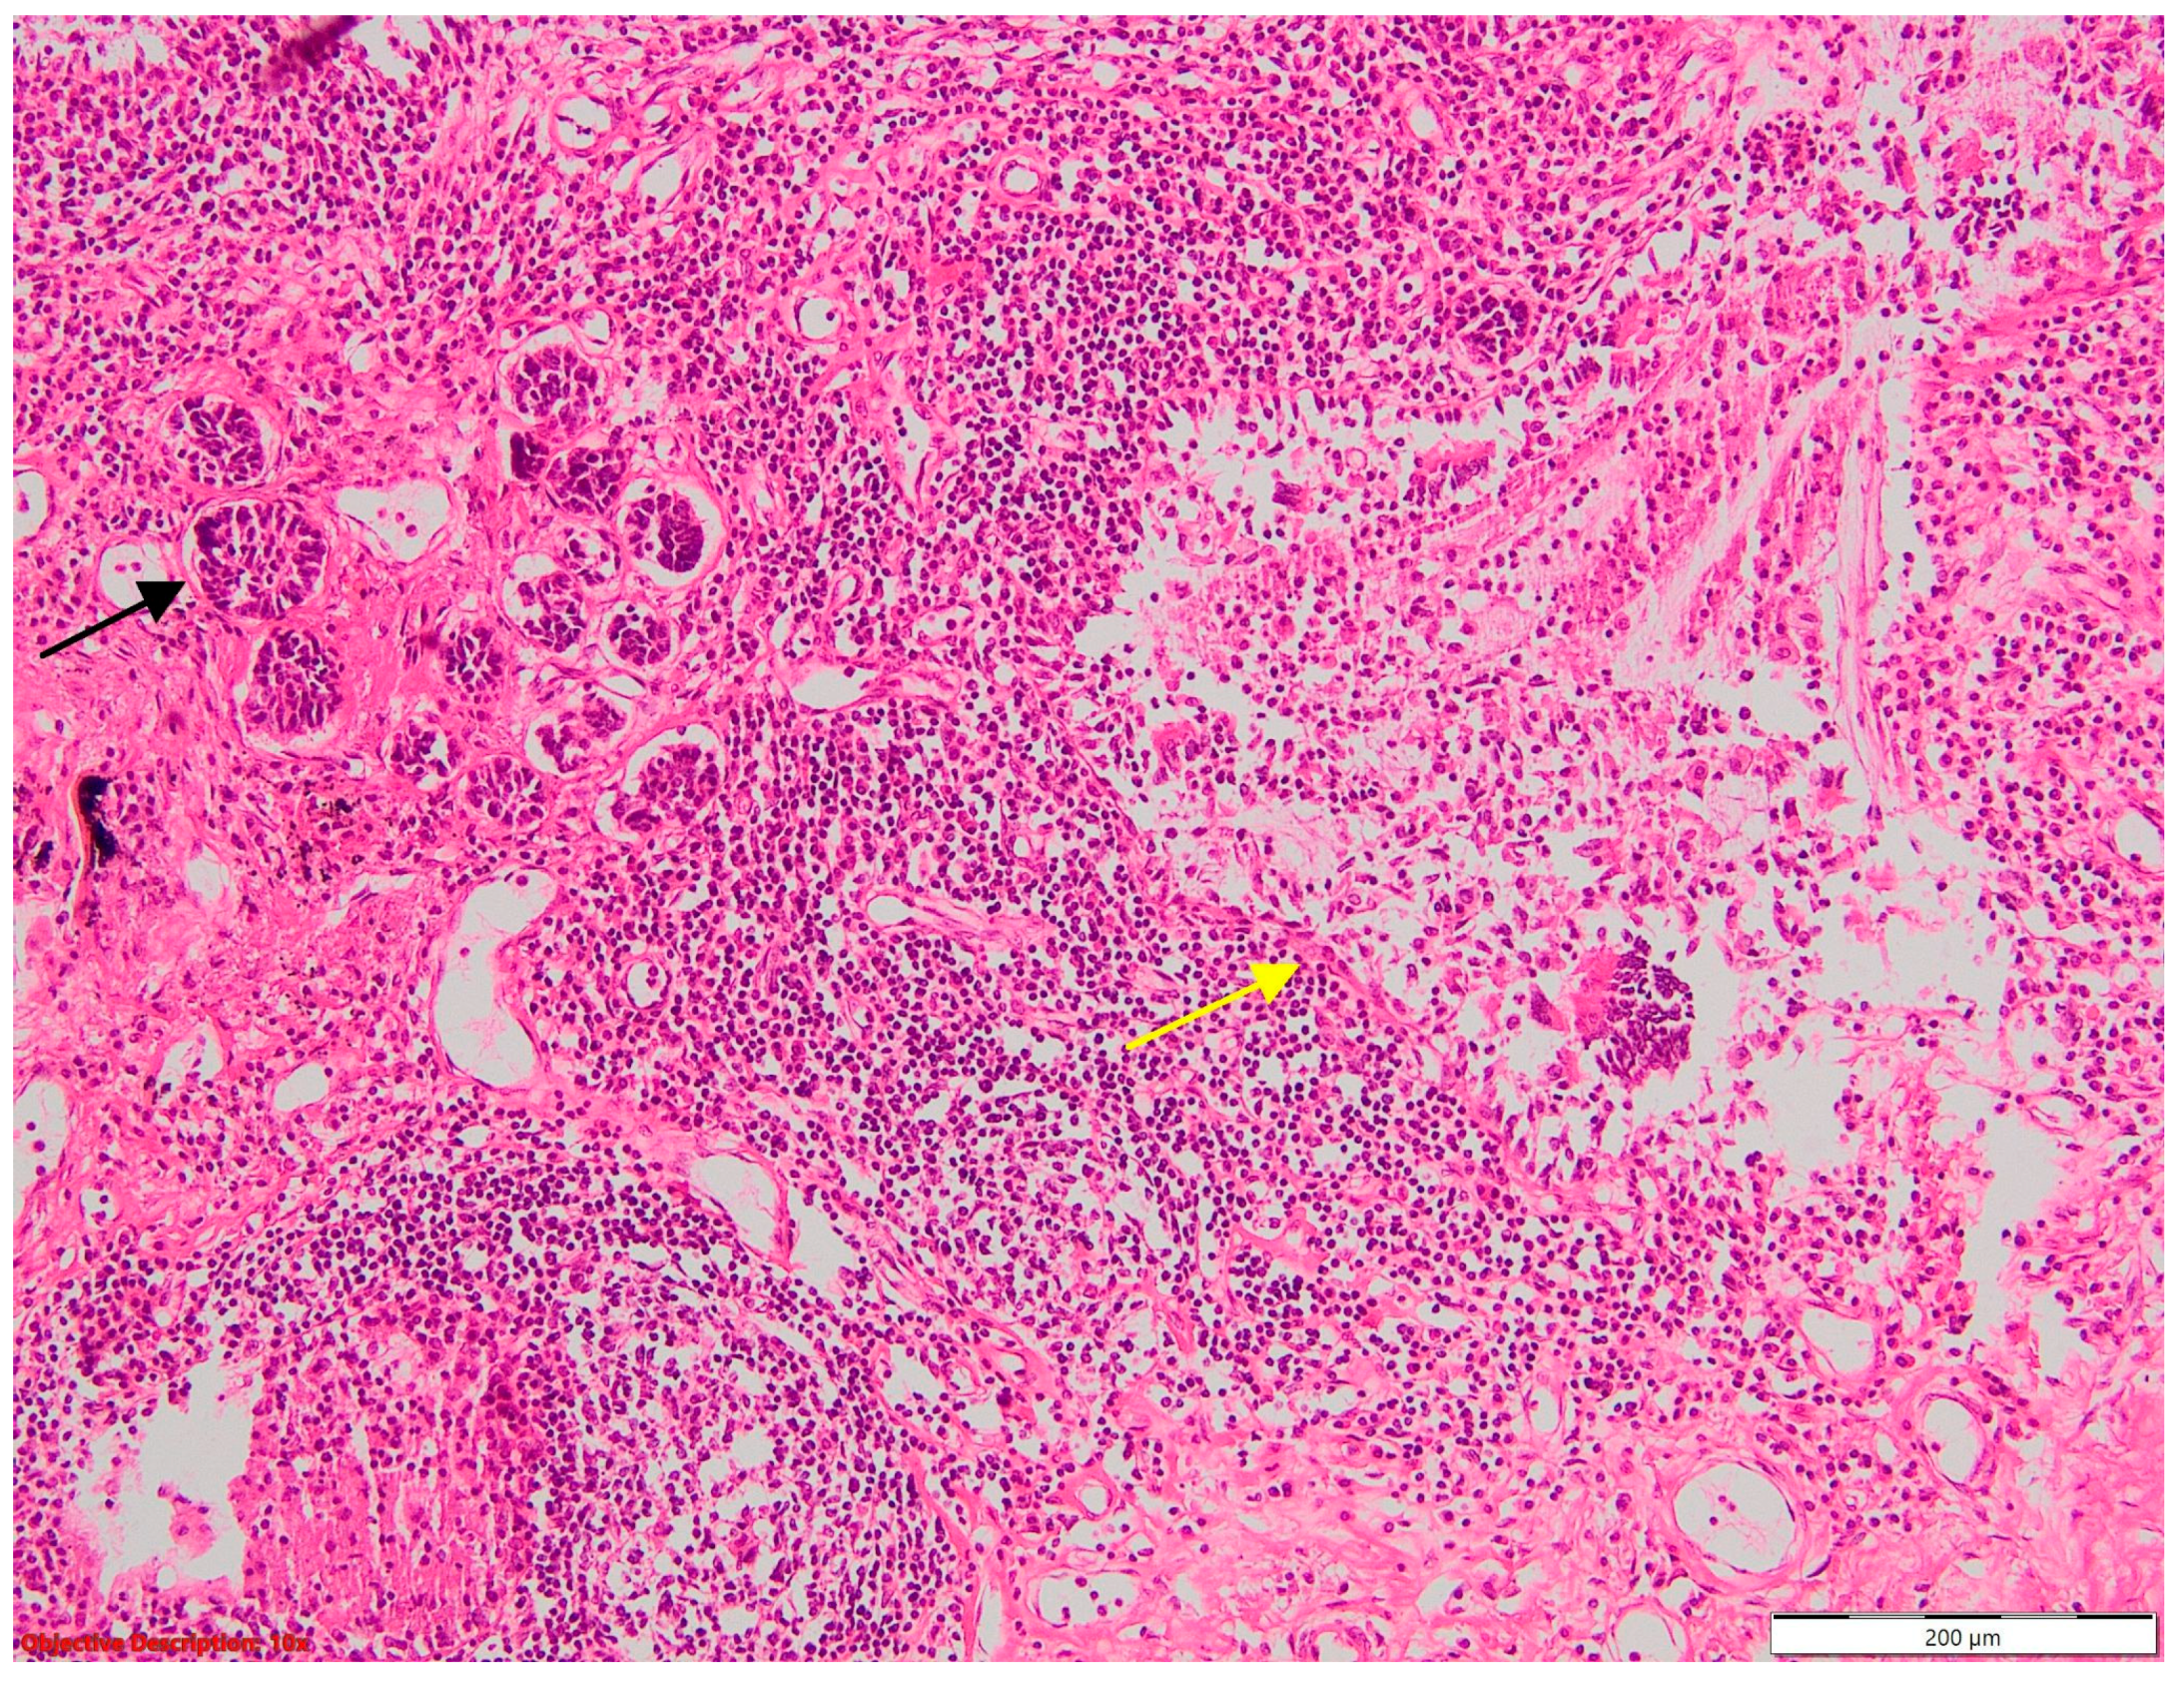

Two of the specimens with fibronodular lesions were associated with multiple NSCLC tumors of different histopathological subtypes: one case presented with adenocarcinoma (one tumor—Figure 6) and a squamous cell tumor (one tumor—Figure 7) and another case presented with adenocarcinoma (one tumor) and large-cell neuroendocrine tumors (two tumors—Figure 8).

When examining the localization of coexisting lesions, a fascinating pattern emerged: a majority of cases (43%) showcased lesions within the same lobe (N = 16) (Figure 10). This intriguing observation raises questions about the accuracy of tumor staging, as lesions within the same lobe may suggest T3 tumor extension, potentially leading to misclassification and subsequent treatment decisions. Furthermore, 27% of cases exhibited lesions concurrently in both the same lobe and lymph nodes. This finding underscores the complexity of lesion distribution and highlights the need for meticulous nodal staging to accurately assess disease spread. In comparison, an additional 27% presented coexisting lesions spanning across different lobes (N = 10), posing challenges in determining the extent of tumor involvement and guiding surgical resection boundaries. Remarkably, only one case featured multiple lesions dispersed across distinct lung lobes and lymph nodes, underscoring the rarity and diagnostic dilemma posed by such multifocal presentations. These findings underscore the importance of the careful consideration of lesion localization in NSCLC staging to minimize staging errors, inform treatment decisions, and improve patient outcomes.

Figure 10.

Coexisting lesions: lung carcinoma (→) and fibronodular lesion (→); HE, 40×.